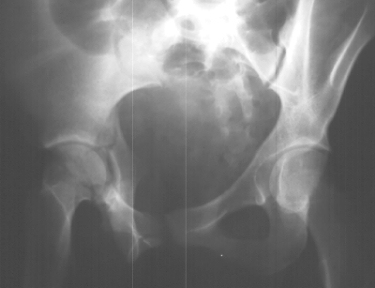

Radiographs:

Radiographs revealed a vertical buckle fracture of the right inferior sacrum, oblique fractures of the superior and inferior rami on the right and a fracture through the medial acetabulum. Obturator and iliac oblique inlet and outlet pelvic views, and a thin cut CT with 3-D reconstruction of the acetabulum were performed. These elucidated a comminuted anterior wall with fracture line extending to the posterior column. The posterior column was non-displaced. The pelvic fracture was non-displaced.

1. Right T-shaped acetabular fracture with anterior wall comminution.